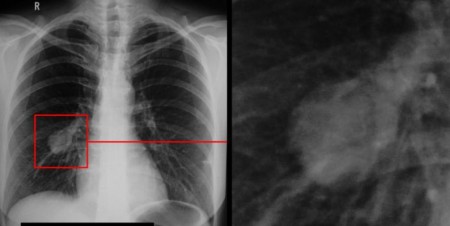

Мужчины в Красноярском крае чаще других в Сибири болеют раком лёгких

Мужчины в Красноярском крае чаще других в Сибири сталкиваются с раком лёгких. Об этом рассказала старший научный сотрудник отделения торакальной онкологии НИИ онкологии Томского НИМЦ Татьяна Полищук.